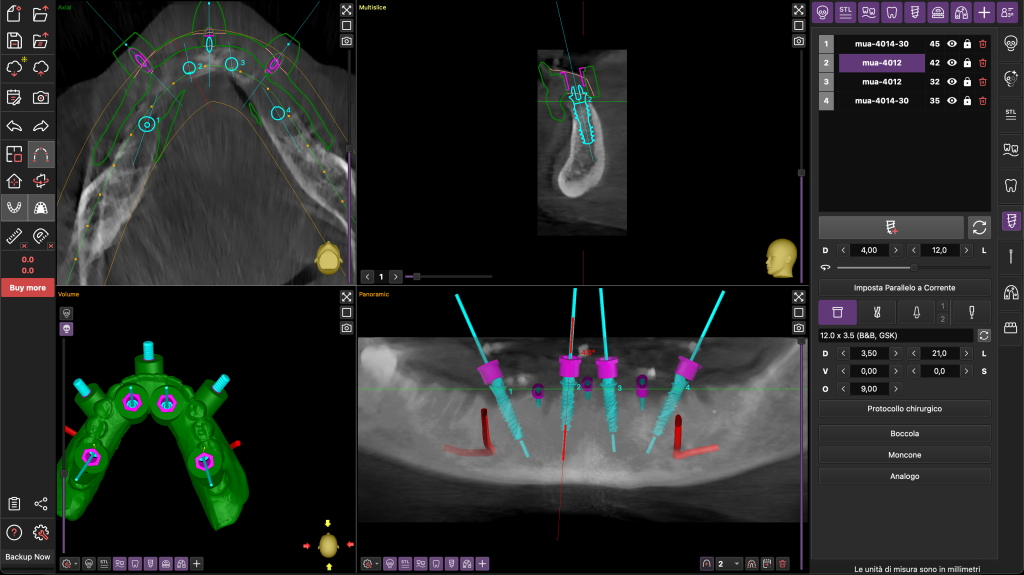

I file STL sono stati poi sovrapposti ai file DICOM della TC Cone Beam con un software dedicato di progettazione guidata B&B Dental. Tramite questo software di chirurgia guidata è stata stabilita la posizione degli otto impianti, da posizionare con l’ausilio di una dima chirurgiche a supporto mucoso fissata con tre pin ossei (Figure 3-4).